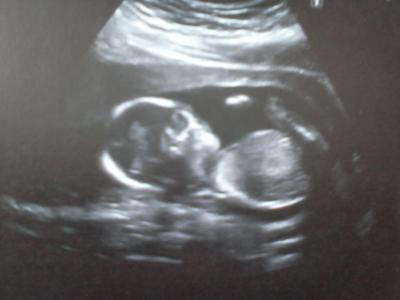

Hallöööööchen ! Danke für die vielen lieben Däumchen von euch. Mit meinen Blutwerten ist alles supi. Hab auch bis jetzt (teu teu teu) keine Röteln gehabt, hab ja keine Immunität mehr. Mein Eisenwert ist auch supi. Muttermund ist zu und ph-Wert ist bei 4. ABER dann.... Ultraschall........... Zwergi natürlich nicht mitgemacht :-( Naja egal, er/sie ist super gewachsen. Arme, Beine und Kopf alles dran :-) Und sieht alles gut aus... Jetzt heißts bis zum 26. April warten da ist dann der 2. große Ultraschall. Und hier noch ein Bildchen von TicTac Ganz liebe Grüße Anna

Bild zu Zurück von der VU und ratet mal wie sich unser Zwerg gezeigt hat ?! - Forum für September - Mamis